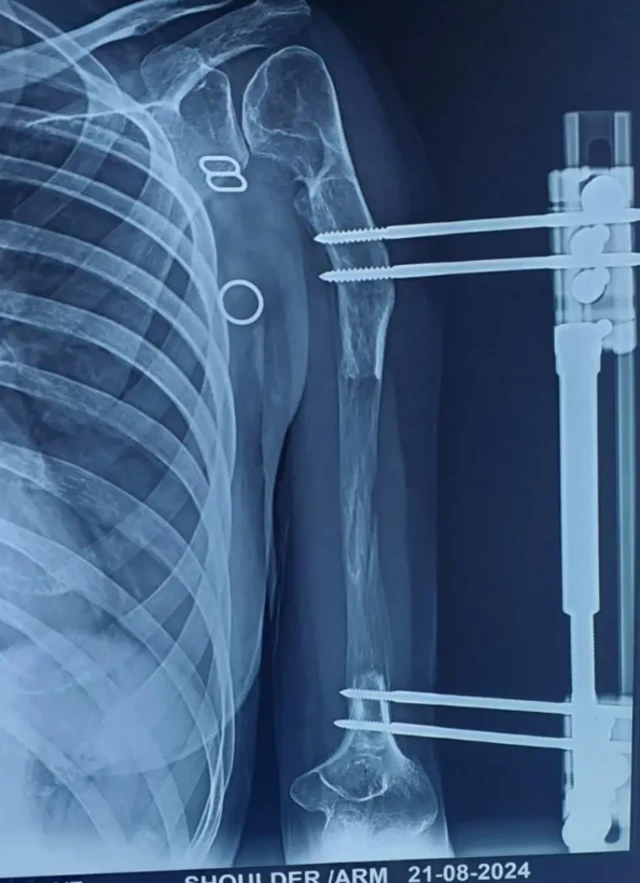

ਡਾਕਟਰ ਸੁਰੇਸ਼ ਕਹਿੰਦੇ ਹਨ, "ਅਸੀਂ ਪਹਿਲਾਂ ਵਿਗਿਆਨਕ ਤੌਰ 'ਤੇ ਵਿਕਾਸ ਸਬੰਧੀ ਨੁਕਸ ਵਾਲੇ ਵਿਅਕਤੀ ਦੀ ਹੱਡੀ ਨੂੰ ਤੋੜਦੇ ਹਾਂ। ਫਿਰ ਇੱਕ ਬਾਹਰੀ ਫਿਕਸੇਟਰ ਮਰੀਜ਼ ਦੀ ਹੱਡੀ ਨਾਲ ਜੋੜਿਆ ਜਾਂਦਾ ਹੈ ਅਤੇ ਪੇਚ ਲਗਾਏ ਜਾਂਦੇ ਹਨ।''

''ਇਹ ਯੰਤਰ ਮਰੀਜ਼ ਦੀ ਚਮੜੀ ਦੇ ਬਾਹਰ ਹੁੰਦਾ ਹੈ। ਜਦੋਂ ਯੰਤਰ ਨੂੰ ਹਰ ਰੋਜ਼ ਘੁੰਮਾਇਆ ਜਾਂਦਾ ਹੈ, ਤਾਂ ਹੱਡੀ ਇੱਕ ਝਿੱਲੀ ਵਾਂਗ ਫੈਲ ਜਾਂਦੀ ਹੈ। ਜਦੋਂ ਤੁਸੀਂ ਇਸ ਨੂੰ ਖਿੱਚਦੇ ਹੋ ਤਾਂ ਹੱਡੀ ਵਿੱਚ ਰਬੜ ਬੈਂਡ ਵਰਗੀ ਲਚਕਤਾ ਹੁੰਦੀ ਹੈ।''

ਸਰਜਰੀ ਤੋਂ ਦਸ ਦਿਨਾਂ ਬਾਅਦ, ਬਾਹਰੀ ਯੰਤਰ ਵਿੱਚ ਪੇਚ ਵਰਗੀ ਬਣਤਰ ਨੂੰ ਕੱਸਣ ਨਾਲ ਹੱਡੀ ਝਿੱਲੀ ਵਾਂਗ ਫੈਲਦੀ ਹੈ।

ਜਦੋਂ ਯੰਤਰ ਦੀ ਪੇਚ ਵਰਗੀ ਬਣਤਰ ਨੂੰ ਦਿਨ ਵਿੱਚ ਹਰ ਛੇ ਘੰਟਿਆਂ ਵਿੱਚ ਇੱਕ ਵਾਰ ਘੁੰਮਾਇਆ ਜਾਂਦਾ ਹੈ, ਤਾਂ ਅੰਦਰਲੀ ਹੱਡੀ ਹੇਠਾਂ ਵੱਲ ਖਿੱਚੀ ਜਾਂਦੀ ਹੈ ਅਤੇ ਵਧਦੀ ਹੈ। ਇਸ ਬਣਤਰ ਨੂੰ ਪੇਚ ਕਰਨ ਦੀ ਪ੍ਰਕਿਰਿਆ (ਪੇਚ ਘੁੰਮਾਉਣ ਦੀ ਪ੍ਰਕਿਰਿਆ) ਇੰਨੀ ਸਰਲ ਹੈ ਕਿ ਮਰੀਜ਼ ਇਸ ਨੂੰ ਖੁਦ ਕਰ ਸਕਦੇ ਹਨ।

ਇਹ ਡਿਸਟਰੈਕਸ਼ਨ ਓਸਟੀਓਜੇਨੇਸਿਸ ਨਾਮਕ ਇੱਕ ਇਲਾਜ ਤਹਿਤ ਕੀਤਾ ਜਾਂਦਾ ਹੈ। ਇਸ ਇਲਾਜ ਵਿੱਚ, ਹੱਡੀ ਪ੍ਰਤੀ ਦਿਨ ਇੱਕ ਮਿਲੀਮੀਟਰ ਦੀ ਦਰ ਨਾਲ ਇੱਕ ਝਿੱਲੀ ਵਾਂਗ ਵਧਦੀ ਹੈ, ਭਾਵ ਇੱਕ ਸੈਂਟੀਮੀਟਰ ਵਧਣ ਵਿੱਚ ਦਸ ਦਿਨ ਲੱਗਦੇ ਹਨ।

ਗੋਮਤੀ ਦੀ ਹੱਡੀ ਨੂੰ 14 ਸੈਂਟੀਮੀਟਰ ਤੱਕ ਵਧਣ ਵਿੱਚ 140 ਦਿਨ ਲੱਗੇ। ਫਿਰ ਖਿੱਚੀ ਹੋਈ ਝਿੱਲੀ ਨੂੰ ਹੱਡੀ ਵਾਂਗ ਮਜ਼ਬੂਤ ਬਣਨ ਵਿੱਚ ਦੁੱਗਣੇ ਦਿਨ ਲੱਗਦੇ ਹਨ, ਭਾਵ - 280 ਦਿਨ।

ਉਨ੍ਹਾਂ ਕਿਹਾ, "ਗੋਮਤੀ ਦੀ ਦਿੱਕਤ ਵਾਲੀ ਬਾਂਹ ਵਿੱਚ ਹੱਡੀ ਪਹਿਲਾਂ 14 ਸੈਂਟੀਮੀਟਰ ਲੰਬੀ ਸੀ। ਹੁਣ, 14 ਸੈਂਟੀਮੀਟਰ ਹੋਰ ਵਧਣ ਨਾਲ, ਇਹ ਕੁੱਲ 28 ਸੈਂਟੀਮੀਟਰ ਲੰਮੀ ਹੋ ਗਈ ਹੈ ਅਤੇ ਆਮ ਵਾਂਗ ਦਿਖਾਈ ਦਿੰਦੀ ਹੈ। ਨਾ ਸਿਰਫ਼ ਹੱਡੀ, ਸਗੋਂ ਚਮੜੀ, ਖੂਨ ਦੀਆਂ ਨਾੜੀਆਂ ਅਤੇ ਨਸਾਂ ਵੀ ਇਸਦੇ ਨਾਲ ਵਧੀਆਂ ਹਨ।''